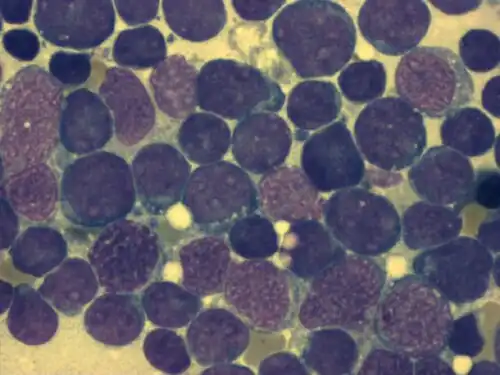

Zytomorphologie

Durch mikroskopische Untersuchung des Knochenmarks oder des Blutausstrichs bei leukämischem Verlauf kann die Diagnose einer akuten Leukämie gestellt werden. Für die weitere Subklassifikation der ALL spielt die Beurteilung der Zellmorphologie im Gegensatz zur AML nur eine untergeordnete Rolle. In der sogenannten FAB-Klassifikation („French-American-British“) wird zwischen drei verschiedenen Morphologien unterschieden (L1, L2, L3). Von Bedeutung ist das nur für den seltenen L3-Subtyp, der mit der „reifzelligen B-ALL“ assoziiert ist. Die reifzellige B-ALL ist eine Sonderform der ALL und kann als die leukämische Manifestation des Burkitt-Lymphoms betrachtet werden (d. h. ein Burkitt-Lymphom mit >20 % oder >25 % Knochenmarkbefall) und wird wie dieses behandelt. Die Unterscheidung zwischen L1 und L2-Morphologie ist dagegen schwierig und selbst sehr erfahrene Hämatologen oder Hämatopathologen kommen hier zu unterschiedlichen Einschätzungen. Klinisch hat die Unterscheidung von L1 und L2 keine Bedeutung.

| Häufigkeit der zytomorphologischen Befunde nach FAB-Klassifikation bei Kindern mit ALL[4] | ||

| FAB L1 | Kleine Zellen vorwiegend mit einheitlicher Größe, gleichförmiges Chromatin, Zellkern nicht sichtbar oder klein, regelmäßig vorfindbare Nucleoli, sehr wenig Zytoplasma, leichte bis mäßige Basophilie, unterschiedliches Ausmaß von Vakuolen im Zytoplasma | 84 % |

| FAB L2 | Große Zellen mit unterschiedlicher Größe, ungleichförmiges Chromatin, Zellkern mit unregelmäßigen Spalten und Kerben, einer oder mehrere oftmals große Nucleoli, variable Größe des Zytoplasmas, mäßige bis oft starke Basophilie, unterschiedliches Maß an Vakuolen im Zytoplasma | 15 % |

| FAB L3 | Große Zellen mit einheitlicher Größe, gleichförmig fein gesprenkeltes Chromatin, ovaler bis runder Zellkern, hervorstechende Nucleoli (auch mehrere), viel Zytoplasma, sehr starke Basophilie, oft hervorstechende Vakuolen im Zytoplasma | 1 % |